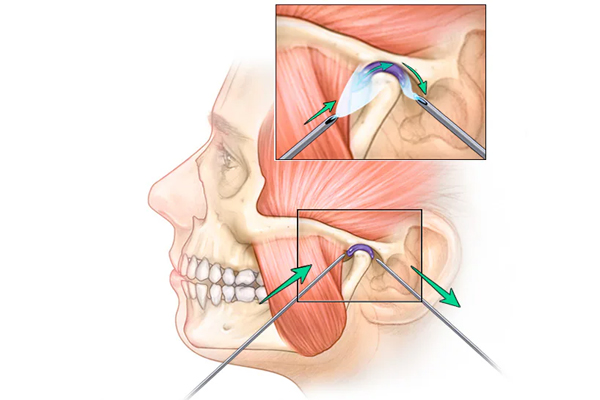

TMJ treatments relieve jaw pain and enhance joint function, especially for those with Temporomandibular Joint disorders. Our advanced machinery, including ultrasound and TENS therapy, effectively addresses pain near the ear and radiating facial discomfort. These therapies, combined with exercises, medications, or devices, provide targeted relief and improved comfort for TMJ patients.